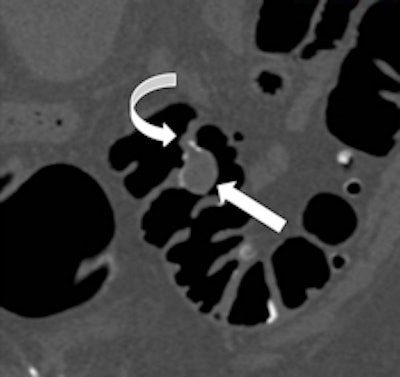

Left: Coronal reformatted view showing a pedunculated polyp of the sigmoid colon. Right: Volume-rendered endoluminal view of the same pedunculated polyp. In both images, the curved arrow indicates the stalk, and the straight arrow indicates the head of the polyp. Images courtesy of Andrea Laghi, MD.As an examination designed for polyp and tumor detection in the colon, CTC has now reached a sufficient level of competency, making the double-contrast barium enema an obsolete examination in 2011, according to fellow ECR presenter Dr. Philippe Lefere, a radiologist at Stedelijk Ziekenhuis in Roeselare, Belgium. As the implementation of CTC moves ahead, general radiologists must become aware this technique can play a significant role by scrutinizing both symptomatic and asymptomatic patients for polypoid and tumoral lesions in the colon.